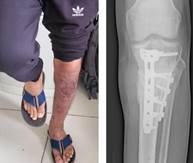

Al día 50, el paciente es dado de alta y acude a controles por parte de cirugía plástica donde se evidencia una buena granulación del tejido. Se planifica 2 semanas después a un nuevo ingreso para realizar injerto de piel en zona de colgajo, el donante será la zona inguinal derecha.

Se procede bajo anestesia peridural, se realiza la marcación del área donante, luego la asepsia y antisepsia y colocación de campos operatorios. Se inicia con la incisión en hoja de laurel de 15x8 cm en región inguinal derecha, luego se realiza la síntesis por planos de área donante y se coloca el injerto de piel sobre la herida, se fijan las suturas con Vicryl 3.0 y Nylon 5.0. finalmente se hace una cobertura con apósito oclusivo.

Figura 7. Injerto de piel

Se planifica un tratamiento con 40 sesiones de los cuales se dividieron en 20 sesiones la primera, luego descanso 10 días y después continuó con 20 sesiones mas más a 2.8 ATA en 90 minutos de presión. Las primeras 20 sesiones iniciaron de lunes a viernes mientras que las otras 20 se dividieron 3 veces por semana alternando los días. En esta secuencia continuó hasta completar las 40 sesiones. Los resultados se evidenciaron en revitalización del tejido, cierre de zona purulenta, formación de callo óseo en zona afectada y recuperación de la movilidad en la extremidad.

Figura 8. Resolución definitiva